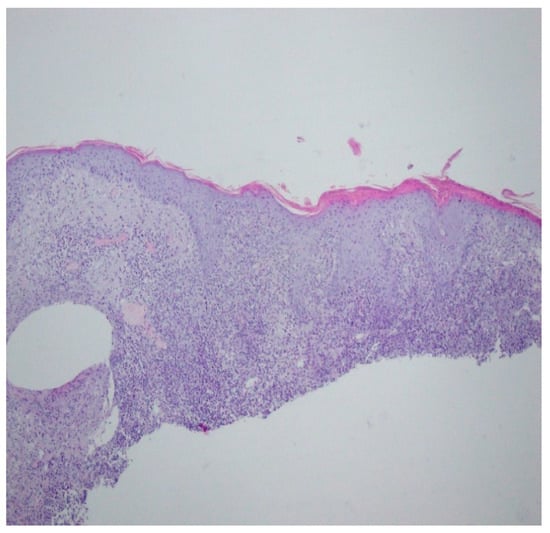

A histopathological examination of the skin lesion performed during hospitalisation revealed a thickened non-regular epidermis with streaky swelling, thinned by lymphocytic and histiocytic inflammatory infiltration with single plasmacytes. Slightly thicker infiltration presented in the area of enlarged vessels of the superficial plexus. There was a lack of characteristics typical for active pyoderma gangrenosum. This clinical picture can be consistent with secondary/tertiary syphilis (Figure 8 and Figure 9).

Figure 9.

Thickened non-regular epidermis with streaky swelling, thinned by lymphocytic and histiocytic inflammatory infiltration with single plasmacytes. Slightly thicker infiltration in the area of enlarged vessels of the superficial plexus. Lack of characteristics typical for active pyoderma gangrenosum. The clinical picture can be consistent with secondary/tertiary syphilis.